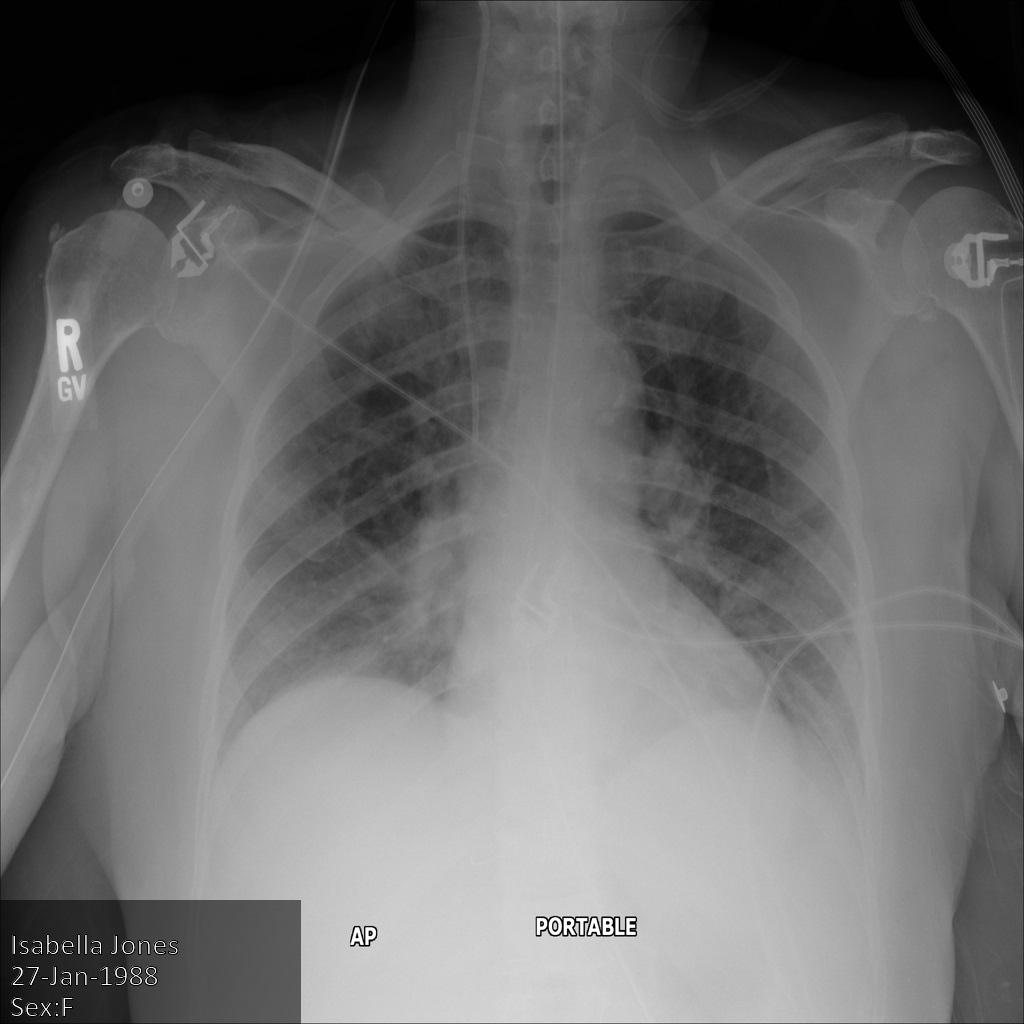

En la siguiente imagen se muestra una radiografía de un paciente sin censurar:

Después de enviar la imagen a la API Cloud Healthcare mediante la opción REDACT_SENSITIVE_TEXT, la imagen se muestra de la siguiente manera:

Puedes ver que ha ocurrido lo siguiente:

- El

PERSON_NAMEde la parte inferior izquierda de la imagen se ha ocultado - El

DATEde la parte inferior izquierda de la imagen se ha ocultado

El sexo del paciente no se ha ocultado porque no se considera texto sensible según los infoTipos DICOM predeterminados.